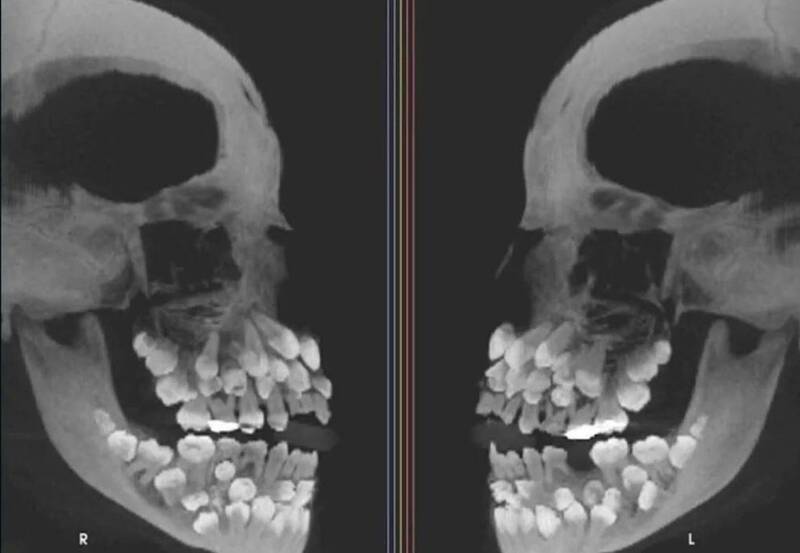

81颗牙齿塞满嘴!女童超罕见X光照曝光

一名年仅11岁的巴西女童,日前因乳牙未脱落就医,没想到X光检查竟发现她的口腔内多达81颗牙齿,远超正常人类牙齿数量,引发当地医界高度关注。

住在巴西的女童原本只计划拔除上排乳牙,医师检查后并无异状,进一步X光检查却惊人发现,她口中竟同时拥有18颗乳牙与32颗恒牙,还塞满超过30颗异常牙齿,这类称为“多生牙”的现象在临床上极为罕见。

研究团队指出,这个案例由巴西米纳斯吉拉斯州胡伊斯迪福拉联邦大学确认,相关结果已刊登于《美国齿颚矫正暨齿颜矫形学期刊》。女童经检测后,并无罹患常见造成多生牙的遗传疾病,比如锁骨颅骨发育不全、加德纳氏症候群或唇颚裂,唯染色体检查显示,他第9对染色体部分片段呈现“倒置”异常,但是否与异常牙齿有关,研究人员尚无定论。